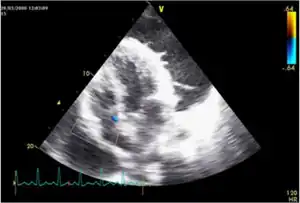

Tuberculous pericarditis is a form of pericarditis.

Pericarditis caused by tuberculosis is difficult to diagnose, because definitive diagnosis requires culturing Mycobacterium tuberculosis from aspirated pericardial fluid or pericardial biopsy, which requires high technical skill and is often not diagnostic (the yield from culture is low even with optimum specimens). The Tygerberg scoring system helps the clinician to decide whether pericarditis is due to tuberculosis or whether it is due to another cause: night sweats (1 point), weight loss (1 point), fever (2 point), serum globulin > 40g/l (3 points), blood total leucocyte count <10 x 109/l (3 points); a total score of 6 or more is highly suggestive of tuberculous pericarditis.[1] Pericardial fluid with an interferon-γ level greater than 50pg/ml is highly specific for tuberculous pericarditis.